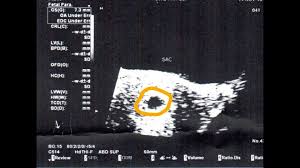

How Long Can An Anembryonic Pregnancy Last - ≥11 days after scan showing gestational sac with yolk sac, but no embryo, or 1.2.. In an anembryonic pregnancy or blighted ovum pregnancy, the sac develops, however, there is no foetus inside. Interestingly, a recent study found significantly fewer trophoblasts in women who had been diagnosed with ectopic pregnancy (an embryo attached outside the uterus) or blighted ovum. In anembryonic pregnancy, a blastocyst is formed from a fertilised ovum, but the fetal pole/embryonever develops, though histologically some fetal material can be demonstrated in most cases. Absent yolk sac when msd >8 mm on transvaginal ultrasound (tvus) 2. The patient may be asymptomatic, presenting for an early pregnancy ultrasound.

A blighted ovum occurs within the first trimester, often before a woman knows she is pregnant. See full list on mayoclinic.org Your body realises the pregnancy is not developing properly and starts to shed blood and tissue from the uterus. If you experience multiple consecutive miscarriages, talk with your doctor or other care provider to identify any underlying causes. An ultrasound will show an empty gestational sac. What are the signs and symptoms of anembryonic pregnancy? A pregnancy test may be positive because the early embryo secretes a pregnancy hormone human chorionic gonadotropin (hcg) until the embryo stops developing and fails to implant. See full list on mayoclinic.org Because a blighted ovum still makes hormones, it can show up as a positive pregnancy test. In anembryonic pregnancy, a blastocyst is formed from a fertilised ovum, but the fetal pole/embryonever develops, though histologically some fetal material can be demonstrated in most cases. See full list on mayoclinic.org May 19, 2020 · about 15 percent of all pregnancies end in miscarriage before 13 weeks of pregnancy. ≥11 days after scan showing gestational sac with yolk sac, but no embryo, or 1.2.

Mar 01, 2018 · natural expulsion may take up to two weeks. A blighted ovum eventually results in miscarriage. An ultrasound will show an empty gestational sac. A blighted ovum will cause a miscarriage usually at 7 to 12 weeks of pregnancy. May 19, 2020 · about 15 percent of all pregnancies end in miscarriage before 13 weeks of pregnancy. In an anembryonic pregnancy, however, the trophoblast attaches itself to the uterus, but the blastocyst never fully forms. Due to falling hcg levels, the clinical signs of pregnancy tend to subside. When there is no embryo seen on endovaginal scanning in a gestational sac with mean sac diameter (msd) ≥25 mm 4 or 1.

An ultrasound will show an empty gestational sac. A blighted ovum usually occurs early in pregnancy between about week 8 and week 13 sometimes before you even know you're pregnant. See full list on mayoclinic.org What are the signs and symptoms of anembryonic pregnancy? Alternatively, she may present with vaginal bleeding in early pregnancy. If you experience multiple consecutive miscarriages, talk with your doctor or other care provider to identify any underlying causes. Absent yolk sac when msd >8 mm on transvaginal ultrasound (tvus) 2. See full list on radiopaedia.org